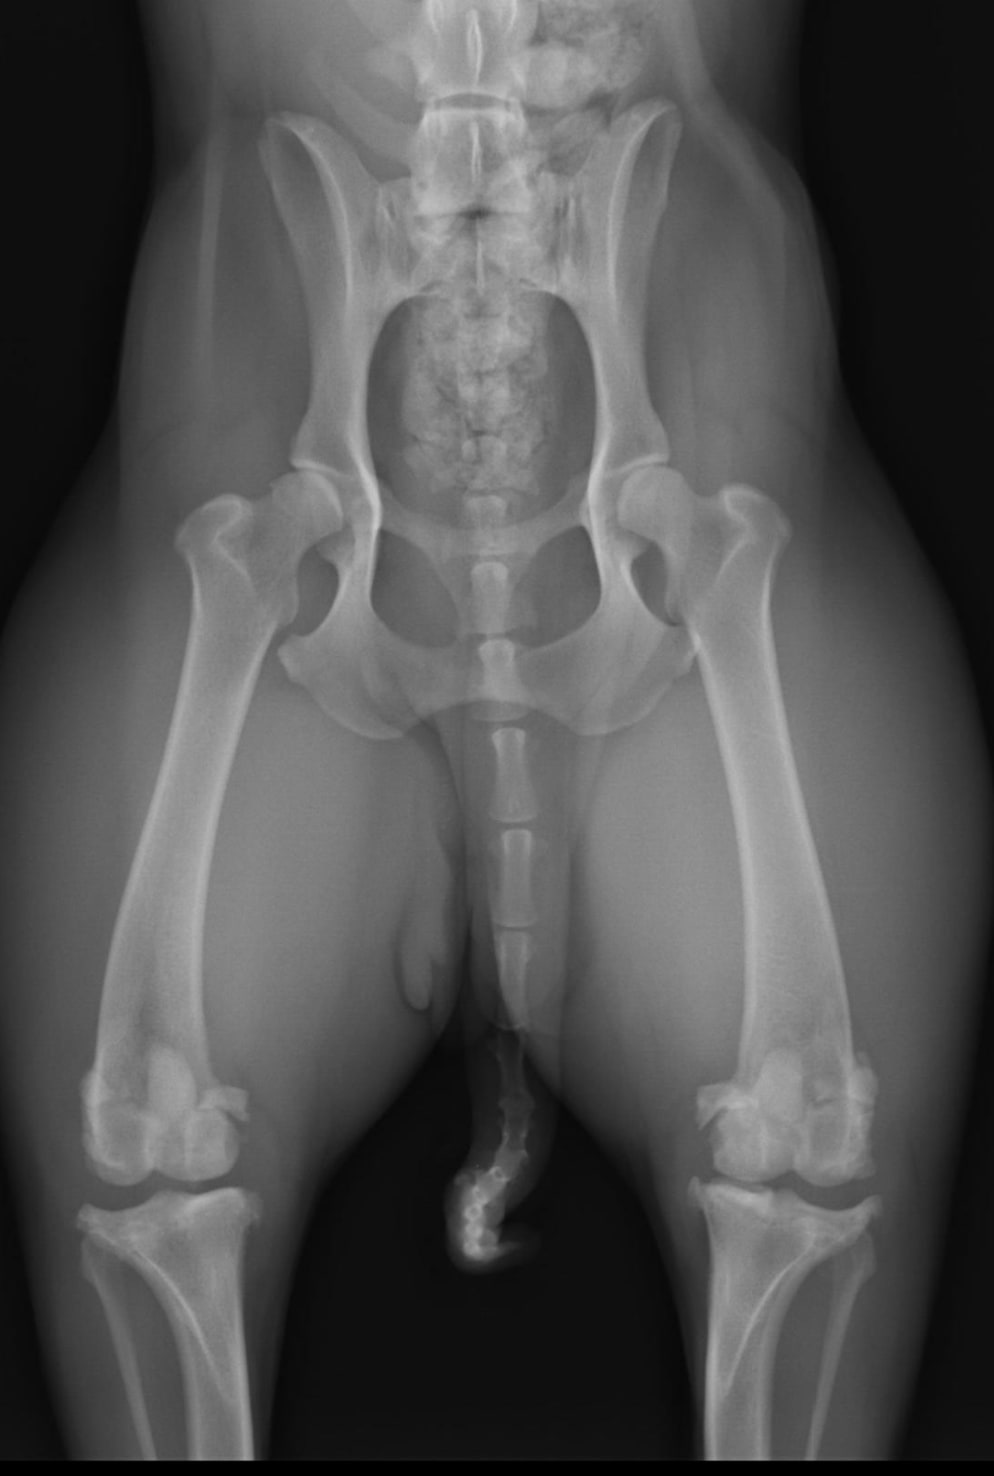

Hello, I was told that my 9 y/o girl has arthritis. She still fetches and climbs up and down stairs without signs of pain. Judging from the Xray, how are her hips and knees? I would like an opinion on how advanced is the arthritis. Please see attachments. Should I stop her from running and climbing upstairs? I have been giving her turmeric paste daily for the past year and she is slim. Thank you for your advice.

Her hips are not that bad but that one knee is pretty advanced. It is best to let her keep walking and climbing stairs to keep the joints in motion and prevent her from getting stiff. I would add a glucosamine and chondrotin supplement to help her joints and omega 3 fatty acids also. I would consider adding an anti inflammatory so she doesn’t get painful and can still fetch without paying for it the next day. From there they make other medicines to add but if she is getting around well with no lameness then I would wait until signs develop further